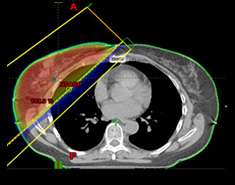

Breast Cancer | SpringerLink